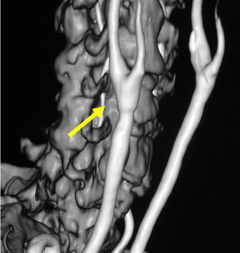

写真左:術前頚動脈狭窄所見

写真右:術後所見 外科手術によって頚動脈狭窄は改善している